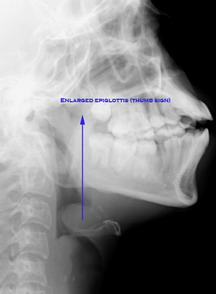

Plain x-ray soft tissue of neck shows enlarged epiglottis ("Thumb sign"), and absence of deep well defined vallecula ("Vallecula sign").

Xray neck showing Thumb sign